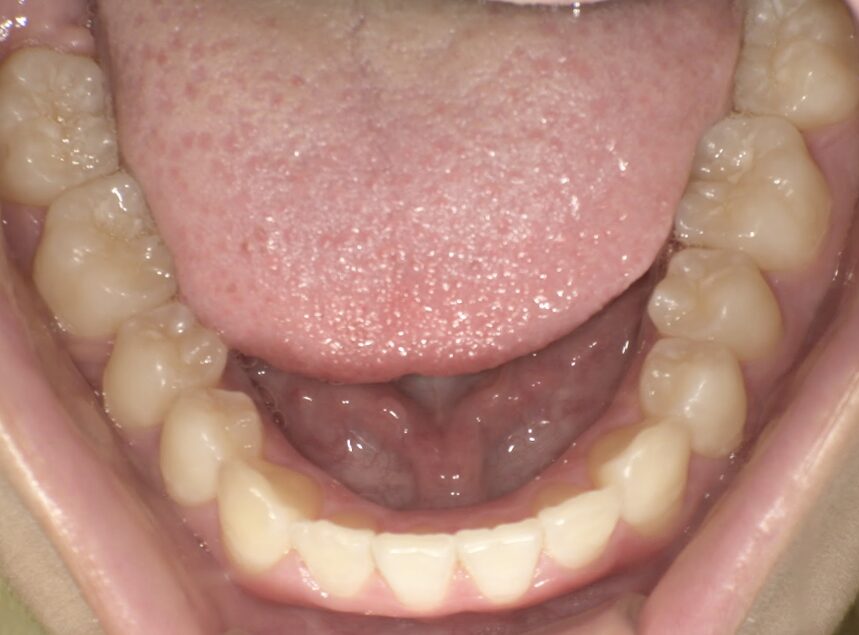

クロスバイト

治療前

ガタガタを主訴に当院を受診され、右上2番にクロスバイトを認めました。IPRを使用してマウスピース型矯正装置(インビザライン)を使用し改善を行いました。